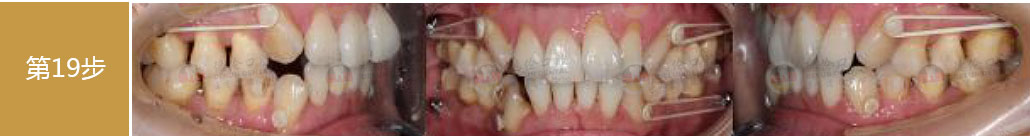

- 【診斷】

骨性Ⅱ類高角伴擁擠

上頜前突、下頜后縮、下前牙唇傾

下中線右偏2.5mm,21 35°扭轉(zhuǎn)13低位

打造醫(yī)生:德倫口腔正畸中心熊小琴主任

- 【治療方案】

拔除3顆多余的咬合不正的智齒,通過支抗釘控制

失狀向和垂直向,推上、下牙遠(yuǎn)移解決擁擠改善前

突,使整個(gè)頜平面逆時(shí)針旋轉(zhuǎn),改善了下頜后縮的

情況

矯治前后對(duì)比

牙列整平排齊,前牙內(nèi)收;覆蓋、覆合正常;尖牙和磨牙達(dá)到中性關(guān)系;上下中線對(duì)齊;下頜后縮改善